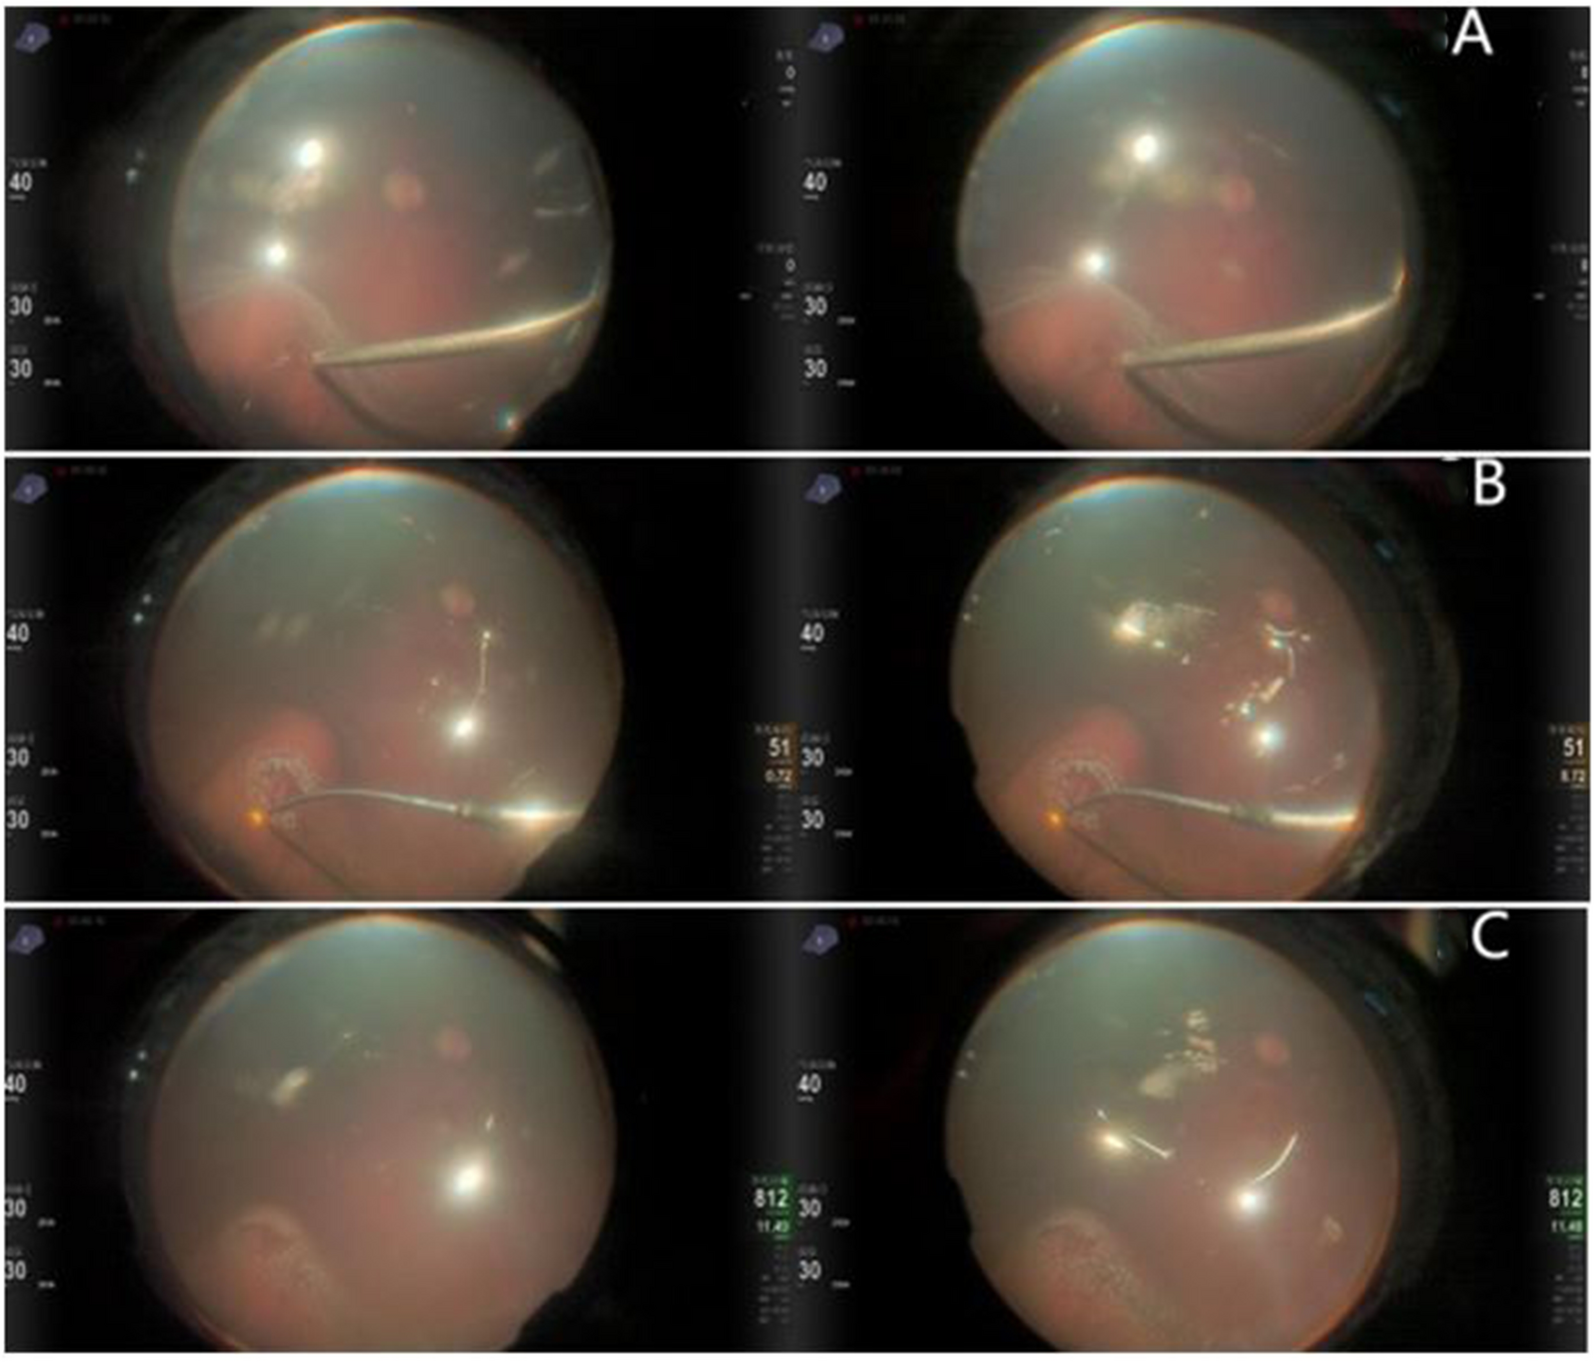

Second, air-filled eyes, especially phakic or pseudophakic eyes [1], have poorer visualization under a microscope, which hinders the application of PFCL-free technology. The 3D visualization system is a good strategy to overcome this difficulty. It is superior to traditional microscopy in many aspects, such as clearer intraoperation visualization, lower endoillumination level, wide-field view, and optimized ergonomic design. The 3D visualization system can improve the magnification (48% higher than conventional microscopy), depth perception (five times better), and resolution (42% increase) by real-time digital signal processing. The digital amplification tool allows sharper, clearer images of high resolution at half the endoillumination levels used in traditional microscopes, reducing the phototoxic damage to the retina [5, 6]. In our experience, at least 50–55% light intensity was required for the conventional microscope to perform PPV, while 30–35% light intensity was enough in the 3D surgeries, and the visual field was much brighter than the conventional microscope. In this study, the 3D visualization system offers a good vision in an air-filled eye, so that intraocular manipulations under air are feasible. After peripheral vitreous is thoroughly shaved, a careful peripheral search with scleral depression and endoillumination is performed. Laser photocoagulation of the degenerative area within the attached retina is completed first, then the SRF is aspirated by fluid–air exchange, followed by laser photocoagulation in the detached region (Fig. 3).

Fig. 3

Images of fluid–air exchange and laser photocoagulation. A SRF is aspirated by fluid–air exchange through the original retinal break; B, C laser photocoagulation around the retinal break and degenerative area